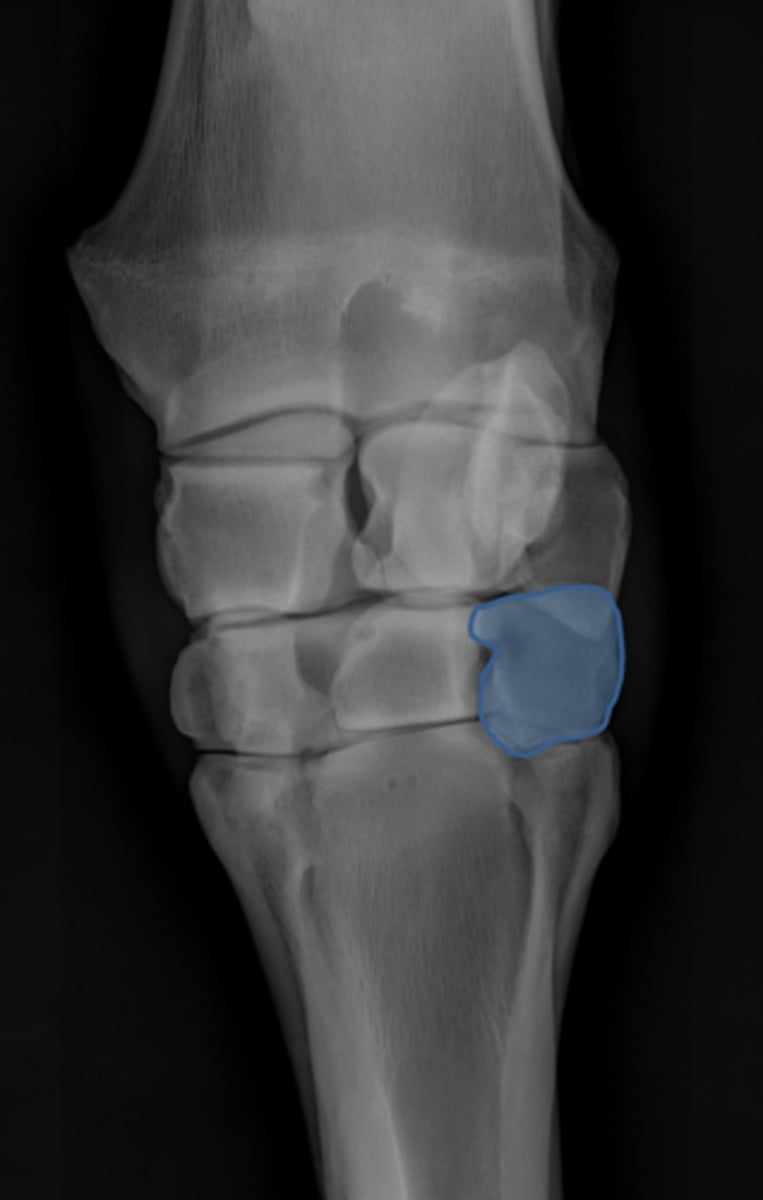

DLPMO

ID view of carpus

Accessory carpal bone

Radial carpal bone

Intermediate carpal bone

Ulnar carpal bone

Second carpal bone

Third carpal bone

Fourth carpal bone